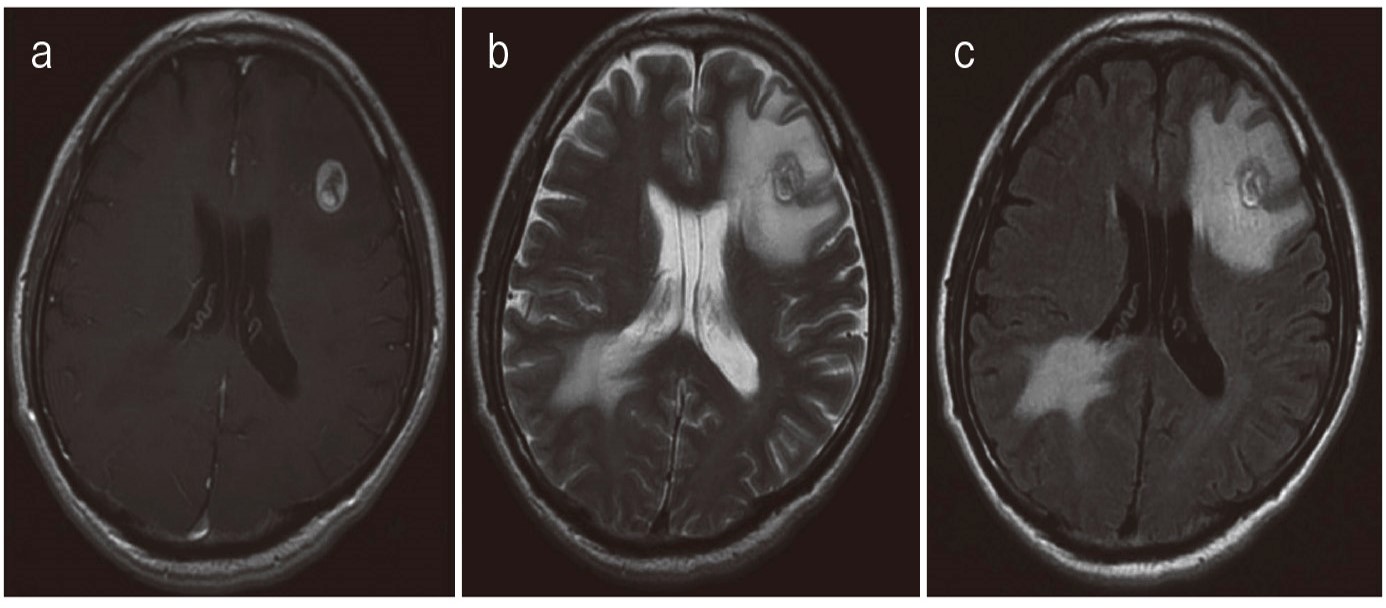

- 腫瘍の位置を特定するためのCT、MRI、陽電子放出断層撮影法(PET)スキャンなどの画像検査